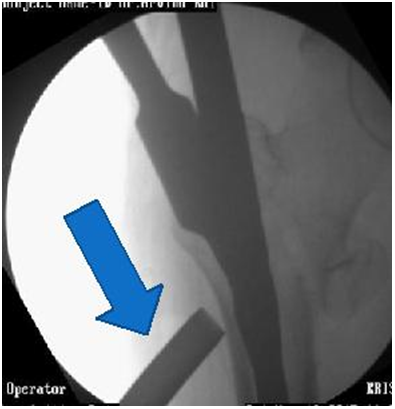

4. Often has 2 Screws in head.  Lag screw and hip pin.  Controls rotation well (Figures 2 & 3).

Figure 2 PFN Biomechanically stronger than DHS.

Figure 3 Excessive collapse with DHS within first week. ?Due to lateral wall comminution.